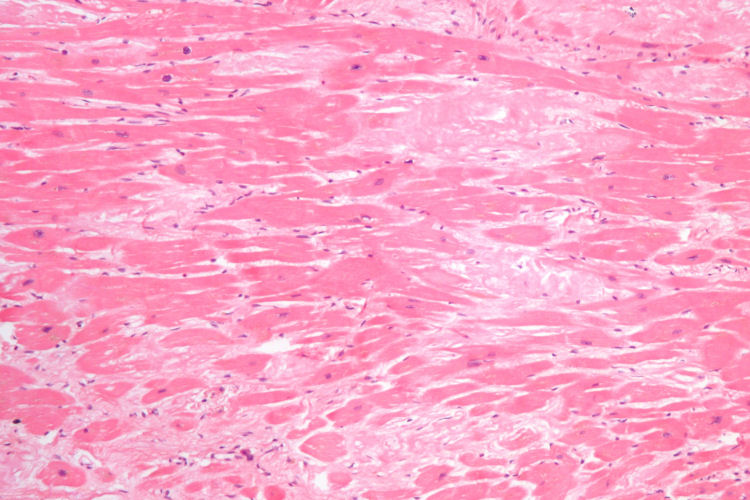

Cardiac amyloidosis

Source: Cardiac amyloidosis intermed mag he.jpg Date: 4 December 2009 Author: Nephron Licence: Creative Commons Attribution-Share Alike 3.0 Unported